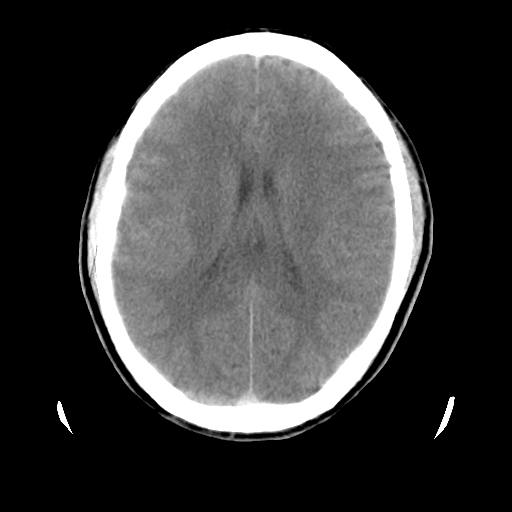

男,51岁,头外伤一小时,呕吐两次。

蛛网膜下腔出血 脑肿胀

左侧颞部硬膜外;蛛网膜下腔出血 ;脑肿胀

1)左侧中颅窝蝶骨翼后方硬膜外血肿。2)左侧颞顶部硬膜下血肿。3)蛛网膜下腔出血。4)左侧筛窦及双侧蝶窦炎症(或积血)。5)左侧额部头皮软组织肿胀。

蛛网膜下腔出血

左侧硬膜外 下血肿  硬膜下血肿影不出外是蛛网膜下腔出血

左颞顶不头皮血肿,左侧颞不硬膜(下)血肿,蛛网膜下腔出血

1:左侧硬膜外及硬膜下混合血肿。2:蛛网膜下腔出血。3:左额部少量颅内积气?

左颞部硬膜外血肿,蛛网膜下腔出血,副鼻窦积液.头皮损伤.